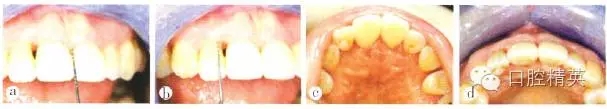

修復(fù)后2周復(fù)查,11間“黑三角”接近消失,鄰間隙關(guān)閉效果基本達(dá)到;到間唇側(cè)牙齦增厚,但仍有2~3 mm高的齦乳頭缺陷,繼續(xù)觀察其生長,并對患者進(jìn)行定期牙周維護(hù)(圖8)。修復(fù)后1年復(fù)查,11間齦乳頭充盈良好,21間齦乳頭充盈程度改善,但尚未完全充滿,上前牙區(qū)唇側(cè)外形輪廓豐滿?;颊呶⑿r,可見上前牙“黑三角”基本消失(圖9)。

a 11間“黑三角”接近消失;b 21間唇側(cè)牙齦增厚,但仍存在2-3mm高的齦乳頭缺陷;c 上前牙腭側(cè)觀;d 上前牙牙合面觀

圖8 修復(fù)后2周復(fù)查

a上前牙區(qū)正面觀,11間齦乳頭充盈良好,21間齦乳頭充盈程度改善,但尚未完全充滿;b上前牙區(qū)牙合面觀,唇側(cè)外形輪廓豐滿:c上前牙區(qū)腭側(cè)觀;d患者微笑像.“黑三角”基本消失;e上前牙區(qū)側(cè)面觀

圖9 修復(fù)后1年復(fù)查